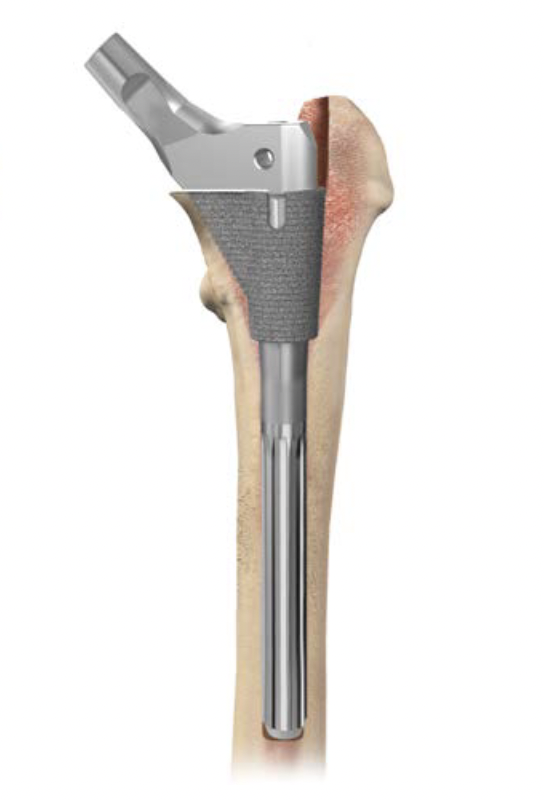

2. Modular uncemented stems to adjust version

- can dial in required anteversion

Depuy S-ROM uncemented modular prosthesis